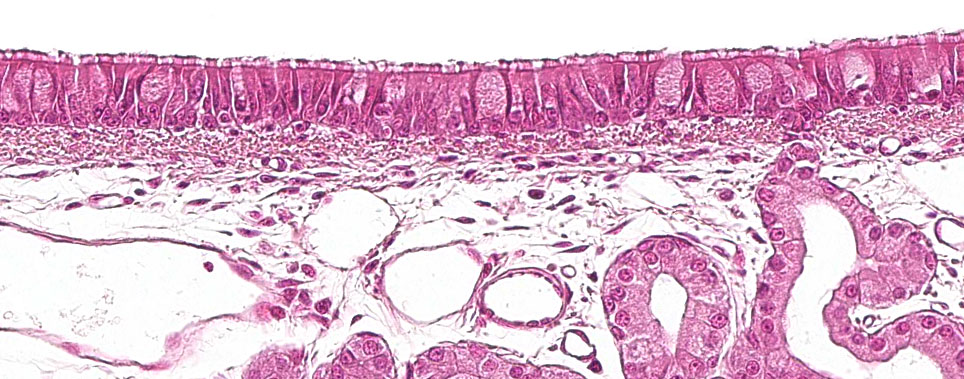

La prima parte dell'apparato respiratorio, la parte conduttiva o le vie aeree, va dalla cavità nasale alle ultime ramificazioni dei bronchioli e comprende anche i seni nasali e paranasali che sono collegati alla cavità nasale, al rinofaringe ed alla laringe. Tutte queste strutture tubolari sono rivestite da un epitelio pseudostratificato ciliato con cellule caliciformi (figura 1), responsabile di uno dei principali sistemi di difesa della mucosa respiratoria, l'apparato mucociliare. Questo sistema è costituito dalle ciglia delle cellule dell'epitelio respiratorio, insieme alle secrezioni delle cellule caliciformi e delle ghiandole sieromucose che compaiono sotto la mucosa respiratoria e la loro funzione principale è quella di eliminare le particelle che entrano attraverso l'aria inspirata. Le ghiandole secernono un liquido limpido, a bassa viscosità e ricco di proteine che è disposto tra le ciglia, formando un mezzo che favorisce il loro movimento verso l'alto. Il muco secreto dalle cellule caliciformi si deposita sulle ciglia e consente alle particelle inalate di aderire. Il movimento verso l'alto delle ciglia spinge il muco verso la parte superiore dell'apparato respiratorio, che può essere deglutito e passare al sistema digestivo, dove viene digerito o espulso all'esterno attraverso la bocca e / o la cavità nasale. Agenti come il Mycoplasma hyopneumoniae, che causa la perdita delle ciglia, o virus come l'influenza suina o il coronavirus respiratorio, che causano la distruzione delle cellule epiteliali, svolgono la loro azione patogena, distruggendo questo sistema difensivo.